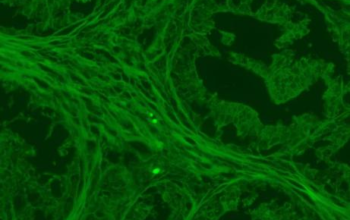

Nhờ sử dụng hệ quang học Infinity plan achromatic objectives, MF31 cho hình ảnh sắc nét đến từng chi tiết nhỏ nhất. Đặc biệt, độ chính xác màu sắc và độ tương phản cao giúp người quan sát nhận diện mẫu vật dễ dàng hơn, ngay cả với những mẫu có độ phát huỳnh quang yếu.

- Bộ lọc huỳnh quang: Blue, Green, UV,… tùy theo ứng dụng

- Quan sát mô bệnh học và tế bào học

- Nghiên cứu vi sinh vật